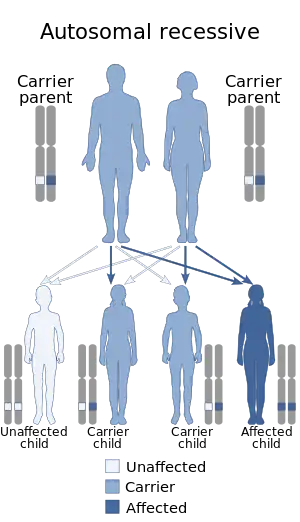

Cenani–Lenz syndactylism is an autosomal recessive congenital malformation syndrome[3][4] involving both upper and lower extremities.

Cenani–Lenz syndactylism is inherited in an autosomal recessive manner.[1] This means the defective gene responsible for the disorder is located on an autosome, and two copies of the defective gene (one inherited from each parent) are required in order to be born with the disorder. The parents of an individual with an autosomal recessive disorder both carry one copy of the defective gene, but usually do not experience any signs or symptoms of the disorder.